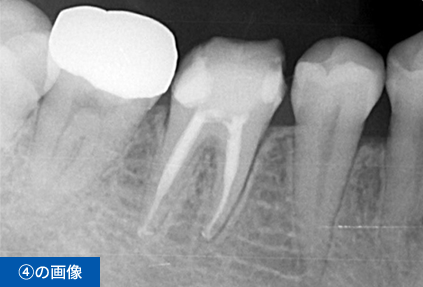

右下6番目の歯が、冷たいものがしみて痛いという主訴でご来院されました。